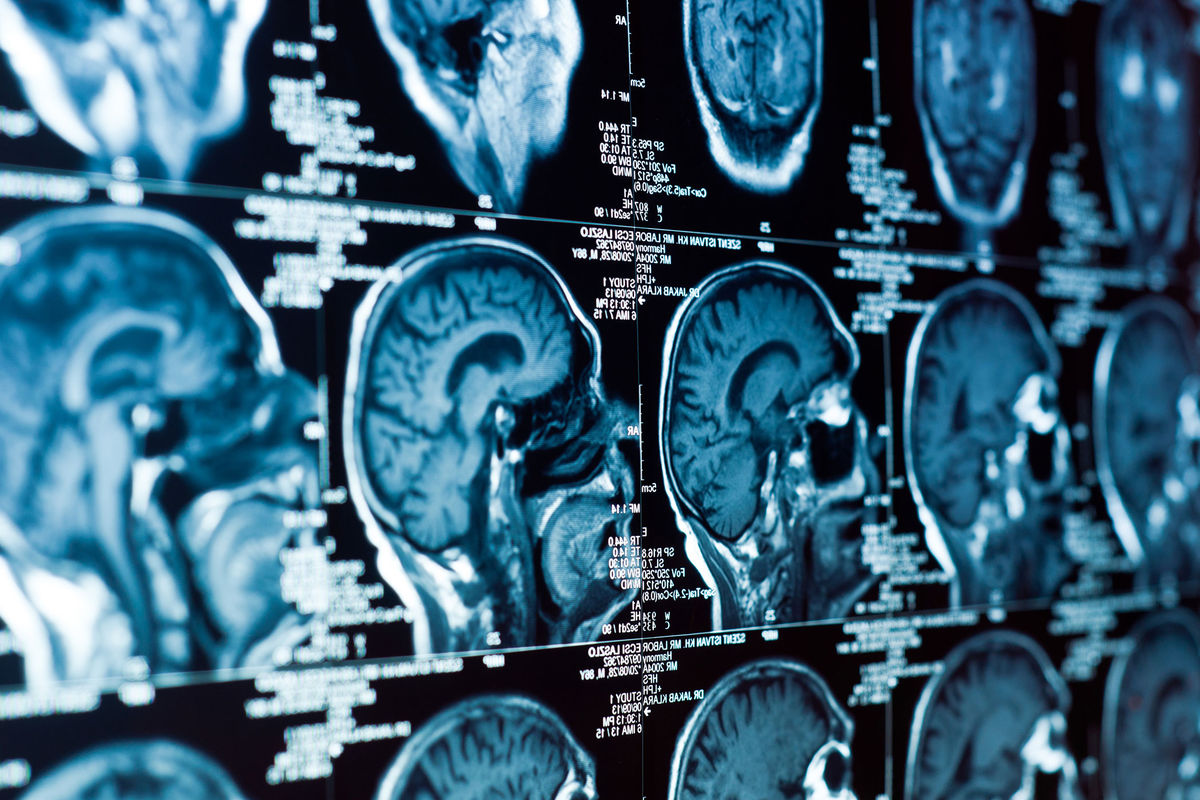

Ученые Колумбийского университета использовали звуковые волны для неинвазивного открытия гематоэнцефалического барьера — естественной "защиты" мозга, которая обычно препятствует попаданию лекарств в опухоли. Результаты исследования опубликованы в журнале Science Translational Medicine (STM).

Несмотря на успехи в лечении некоторых агрессивных опухолей, прогноз при раке мозга у детей остаётся крайне тяжелым: большинство пациентов с глиомой срединных структур живут менее года после постановки диагноза. Основная проблема — гематоэнцефалический барьер, который защищает мозг от токсинов и инфекций, но блокирует действие химиотерапию.